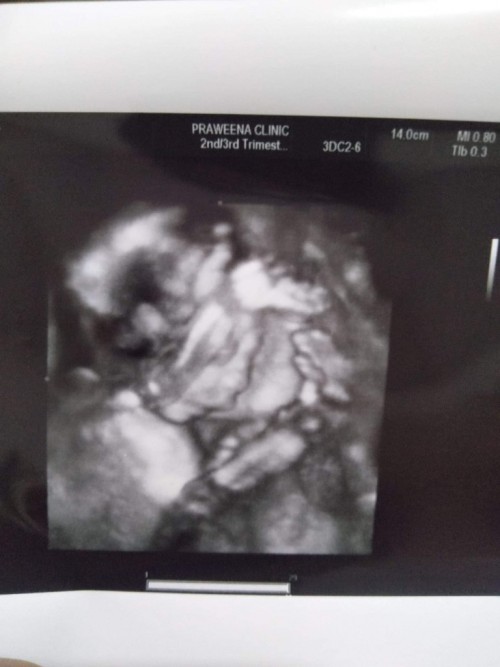

แม่! 🤰💖อวดรูปอัลตร้าซาวด์กัน

โชว์รูปแรกของเบบี้กันหน่อยน้า เพศหญิง👧หรือชาย🧑เอ่ยยย 😍🥰💜 17/09/2563